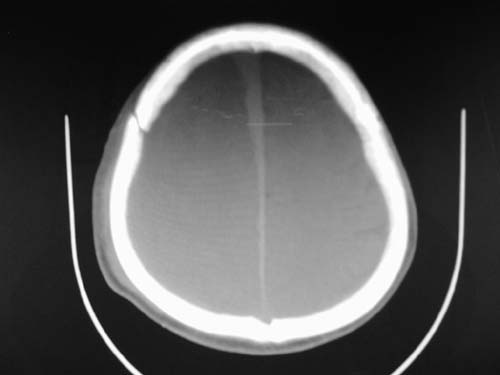

标题: CT17020:是硬膜下的吗?

脑中线内血肿,是硬膜下的吗?

脑中线内血肿——硬膜下血肿。

脑中线内血肿——硬膜下血肿。我们一般认为中线即可是硬膜下,也可是蛛网膜下腔的。边缘锐利,张力高的考虑硬膜下的,边缘模糊的,考虑下腔的。如果有老师有肯定的答案,麻烦下给我发个短信

硬膜下血肿,有颅骨骨折

支持镰旁硬膜下血肿,颅骨骨折,头皮损伤.

这个病人年龄不小吧,右侧脑沟不清,中线结构稍有左移,右侧额颞顶及右镰旁硬膜下血肿,另有蛛血,骨折。

外伤后引起的颅骨骨折、硬膜下血肿、皮下血肿,颅骨骨折引起的矢状窦破裂,形成大脑纵裂内血肿。